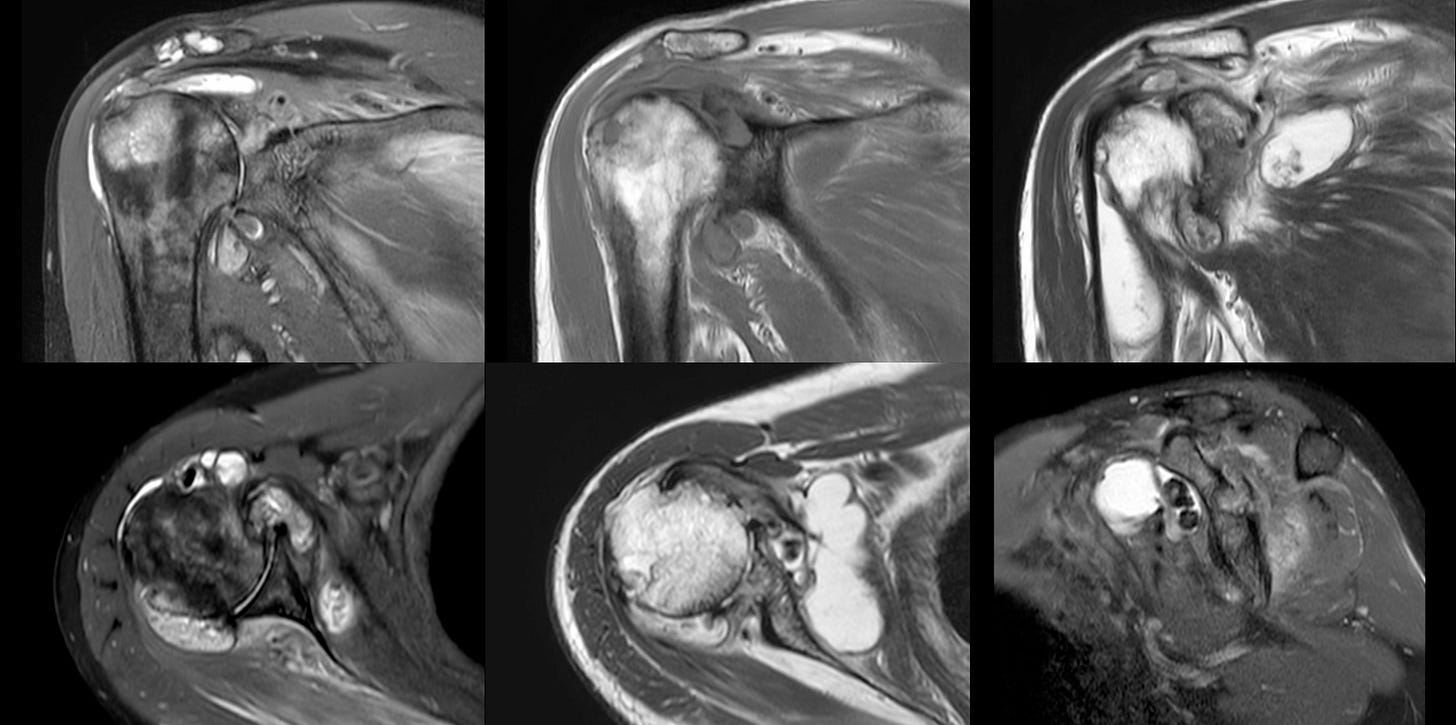

MRI showed a destructive arthropathy, as did a CT scan. Neuroarthropathy was ruled out with an MRI cervical spine.